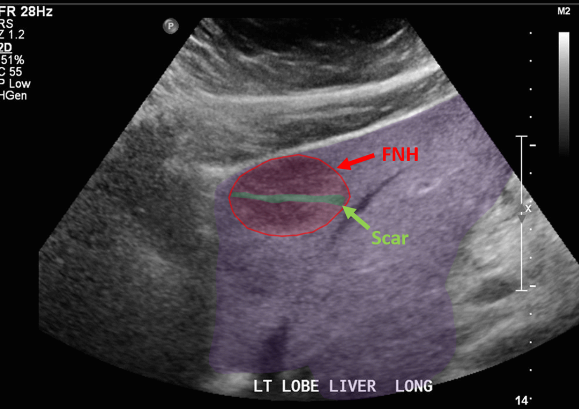

FNH (Focal Nodular hyperplasia) US finding

- hypoechoic lesion with central scar

- fatty liver

위에서 보인 초음파소견처럼 FNH는 경계가 명확한 균일한 종괴이며 내부에 섬유성 반흔이 있다. 에코는 저에코를 갖지만 간혹 고에코나 등에코등 다양하게 나타날 수 있으며 피막이 없다. 도플러상 과혈관성을 보이며 정상 간세포조직을 갖는다. 초음파 만으로 간암과 구별할 수 없으므로 혈액검사, CT 와같이 다양한 검사를 통한 진단이 필요하다.